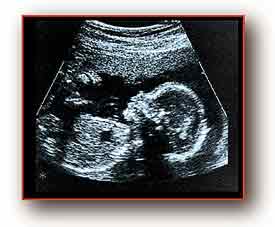

technique to fetuses in the womb. Recently he suggested to a government panel in

the US, the Recombinant DNA Advisory Committee, that the technique to cure a

fatal blood disease called alpha-thalassaemia might first be tried on fetuses

already scheduled for abortion.